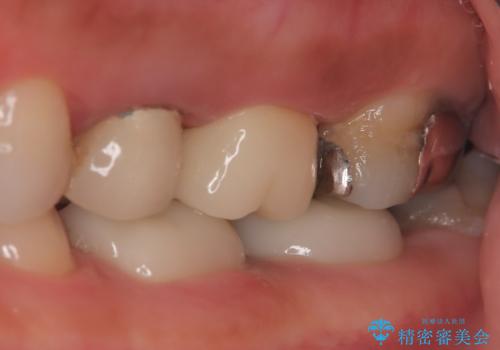

【破折ファイル除去】他院で折れた根管治療の器具をとってほしい

- 他院で折れた根管治療の器具をとってほしいという主訴で来院されました。

マイクロスコープで根管内を観察すると、除去できる状態だったため破折ファイル除去を行いオールセラミッククラウンにて修復治療しております。

- 35万円費用は治療当時の料金となります